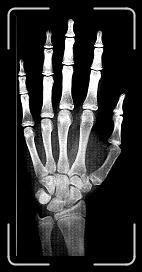

18 9 ANYS

Joaquim Piqueras - Rx- HMI